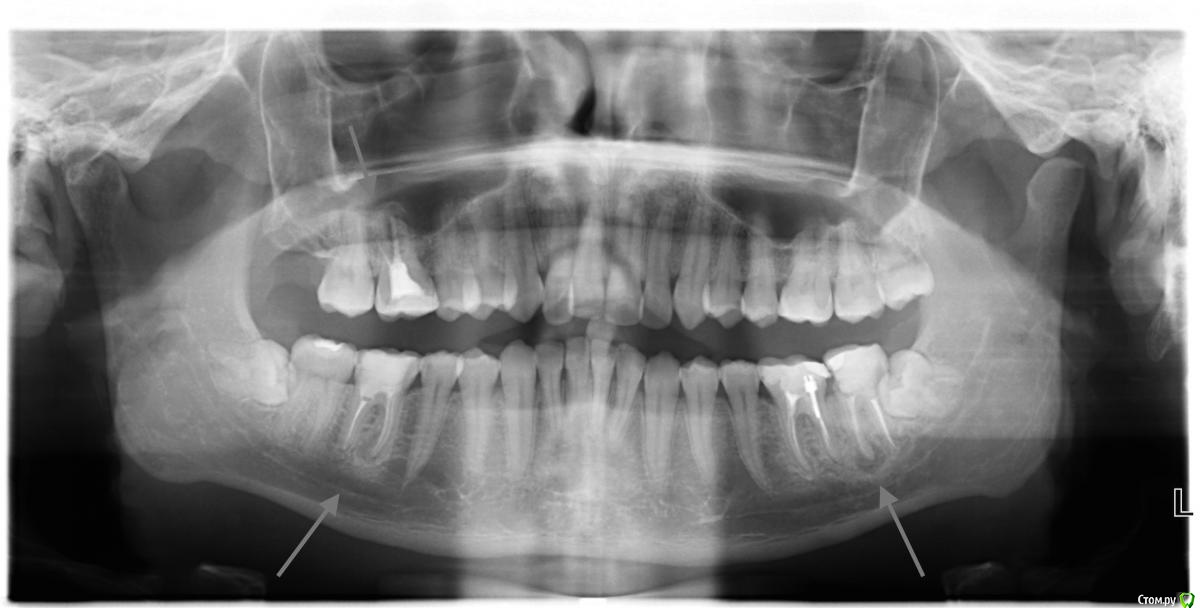

rdin Опубликовано 29 марта, 2015 Поделиться Опубликовано 29 марта, 2015 (изменено) Здравствуйте, уважаемые специалисты! Подобный проект - большое благо для людей. Буду безмерно счастлив, если получу вашу экспертную оценку о моей ситуации. Чтобы я не сделал фатальной ошибки. Года четыре назад пролечил в городской поликлинике несколько зубов. Через год один зуб начал беспокоить и я обратился в платную клинику, в которой мне сделали снимок, показав воспаление вокруг канала. Меня сразу напугали - зуб нужно обязательно удалять. Я вернулся к своему врачу, которая сказала, что увы, от этого воспаления никуда не деться, но это не так критично и если сильно не беспокоит, проще забыть - люди всю жизнь живут с этим воспалением и всё хорошо. Со временем зуб перестал болеть и я забыл про эту проблему, доверившись врачу. Спустя продолжительное время меня периодически стали беспокоить зубы (иногда есть реакция на холодное и горячее). Сегодня я сходил в коммерческую поликлинику, в которой мне сделали панорамный снимок. Воспаление как было, так и осталось - более того, мне кажется, что оно стало больше (прошлых снимков не сохранилось). К еще большему несчастью, у врача имеются подозрения на воспаления каналов у еще двух зубов. Её заключение - можно забить, но лучше все же постараться сохранить зуб, сделав лечение под микроскопом. При этом никто не гарантирует сохранность зуба, вероятность его потери велика, тем более он уже весь перелечен. Когда она узнала о моих планах на брекеты, предложила обратиться к ортодонту, который, возможно, сможет вывести зубы мудрости на место удаленных жевательных зубов, но такая вероятность так же мала из-за очень криво растущих зубов мудрости (которые я собираюсь удалять). За лечение зуба под микроскопом мне объявили 5000 рублей за 1 канал (на каждый зуб до 4 каналов) - это очень внушительная сумма для меня, поэтому важно принять правильное решение, что делать с зубами. Итоговый вопрос мне сложно сформулировать.Я прошу взглянуть на снимок и оценить состояние воспаления каналов. В итоге 2 или 3 восполенных зуба:Что делать с воспалениями? Забить? Лечить под микроскопом (какая цена адекватна?)? Сходить сначала к ортодонту и посоветоваться, возможно ли сдвинуть зубы мудрости? Или проще сразу удалить все зубы и копить денег на имплантанты?Заранее спасибо за вашу экспертную оценку. Я бы, конечно, хотел бы получить консультацию и о других проблемах, которые вы можете увидеть на снимке, но, пожалуй, это отдельная тема. P.S. Мне 25 лет. Изменено 29 марта, 2015 пользователем rdin Ссылка на комментарий

Saymon Опубликовано 30 марта, 2015 Поделиться Опубликовано 30 марта, 2015 (изменено) Зубы в любом случае можно попытаться сохранить.По поводу общих проблем:http://s018.radikal.ru/i525/1503/83/fd8d695032fe.jpg1. Оранжевый цвет - перелечивать каналы.2. Белый цвет - керамические реставрации.3. Красный цвет - удаление 8ых зубов.Для более четкого понимания плана лечения необходимо очная консультация + компьютерная томография. Изменено 30 марта, 2015 пользователем Saymon 4 Ссылка на комментарий